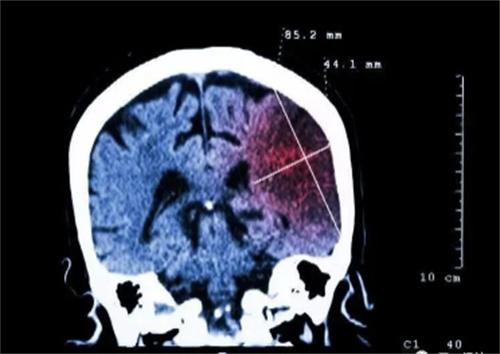

在近几年发生脑梗塞的患者越来越多,而且逐渐向着年轻化的趋势发展,脑梗和生活中很常见的一些不良习惯有着直接的关联性,除了不良的生活会引起脑梗,部分脑梗竟然是吃出来的,在厨房中三种调料的滥用就是发生脑梗的帮凶,这三种材料暗藏危机,经常喜欢吃高盐、高油、高糖的人群,有很大的几率会患高血压和脑梗。

经常吃高油食物,会使人的血液中含有的甘油三酯增多,血液变稠,逐渐形成斑块沉积在血管壁上,时间长了就会发生脑梗,长期摄入高糖的饮食,会使人出现脂肪肝,体内糖分过多人体的肝脏就会释放大量的血脂,从而形成高脂血症,大大增加脑梗的风险。